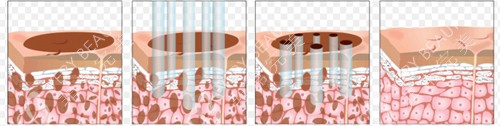

手术当天,护士把我推进手术室,麻醉师温柔地跟我聊天,缓解我的紧张。等我醒来时,已经躺在病房里,脸上缠着厚厚的纱布,只露出眼睛和嘴巴。护士告诉我,手术很成功,SMAS 层折叠得很到位,接下来要好好护理。术后前三天,脸又肿又胀,只能吃流食,护士每天都会来帮我换药,还教我用冰袋轻轻冷敷消肿。

术后第七天拆线,拆开纱布的那一刻,我激动得差点哭出来。下垂的苹果肌提上去了,眼角的皱纹淡了好多,下颌线也清晰了!更让我惊喜的是,耳前的切口真的很隐蔽,不仔细看根本发现不了。王医生叮嘱我,修养期要避免做夸张的表情,按时涂祛疤药膏,三个月内不要用力揉搓面部。